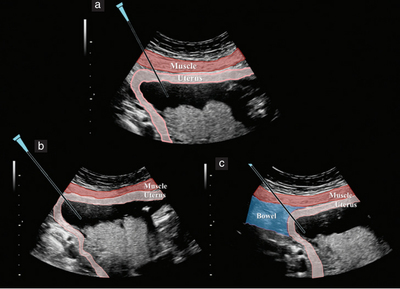

为胎儿做性别审定固然是一种医学需求,但本身也存在风险。除了绒毛穿刺术外,羊膜穿刺术和脐血穿刺术也是有创的审定检查方法。这两种方法审定胎儿性别都是在孕中期中止,存在出血、羊水渗漏、流产,以致损伤胎儿以及发作宫内感染和胎儿死亡的风险。目前,超声检查固然对胎儿发育尚未构成不良影响,但准确率低。因此,假设不是基于胎儿可能发作遗传病要素的思索,医生普通不会为孕妇展开性别审定。